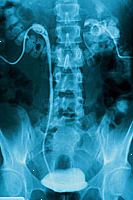

Intravenózní pyelogram, také volal intravenózní urografie, je diagnostický rentgenový ledvin, močovodů, močového měchýře a. Je-li kontrastní barvivo aplikován intravenózně (IV), se močových cest objeví velmi jasně, která není vidět na pravidelných rentgenových paprsků. Intravenózní pyelogram může být provedeno z mnoha důvodů, včetně následujících:

Jako kontrast barvivo se pohybuje do a přes ledviny, močovodů, močového měchýře a může rentgenové záření pořízené v krátkých intervalech zachytit jeho pohyb. Zpoždění v kontrastní barvou pohybující se močového systému může znamenat obstrukci (ucpání) v průtoku krve ledvinou nebo špatnou funkcí ledvin.

Radiolog pak může posoudit funkci a detekovat abnormality močového systému. Tato zkouška se obvykle uloží jako jeden z prvních testů v případě podezření na onemocnění ledvin a močových cest.